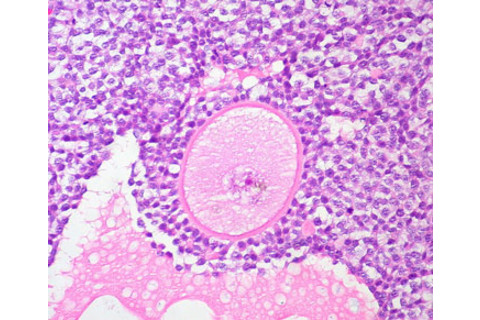

A developing human egg.

Image courtesy of euthman / flickr